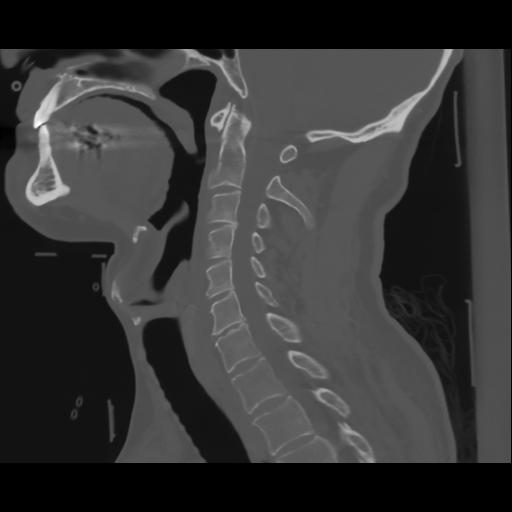

14 P.BLANDAS,,Sagittal,2.000,P.BLANDAS,Sagittal,